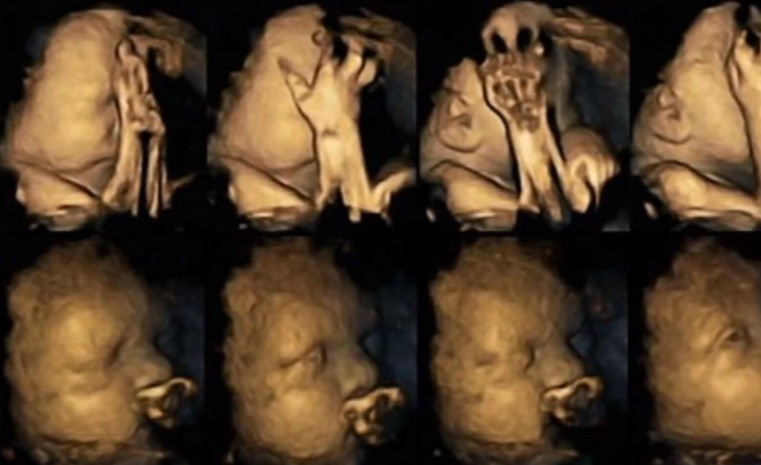

Reissland se dedicó a monitorizar las imágenes 4D de bebés de 20 madres fumadoras para compararlas con las imágenes de bebés de madres o-fumadoras.

Escaneó cómo el bebé se siente cuando la madre fuma en diferentes etapas del embarazo y las imágenes son sorprendentes y desmoralizantes: los bebés de las madres adictas al tabaco (las mujeres estudiadas fumaban hasta 14 cigarrillos diarios) hacen todo tipo de gestos y muecas de descontento y desagrado, se podría decir incluso que de dolor y estrés: se tocan la cara y la nariz mucho más, y mueven la boca con más frecuencia que los demás bebés, de gesto tranquilo.